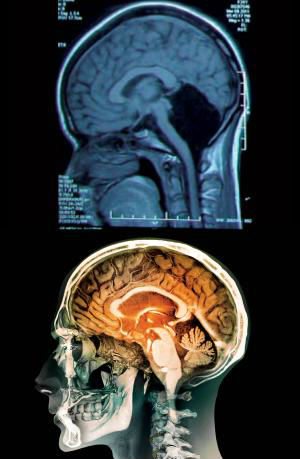

Doctorii şi-au dat seama rapid care-i problema, în urma unei tomografii: îi lipsea cerebelul. Spaţiul în care trebuie să fie această parte a creierului este lipsit de ţesut, plin cu un lichid cerebrospinal, care asigură o protecţie împotriva bolilor.

Cerebelul, numit şi creierul mic, este localizat sub cele două emisfere. Reprezintă circa 10 procente din volumul total al creierului, dar conţine 50% din neuronii unei persoane.

Sarcina principală a cerebelului este aceea de a controla mişcările şi echilibrul. De asemenea, se consideră că este implicat în învăţarea anumitor mişcări şi în vorbire. Afecţiuni ale cerebelului pot duce la probleme cu mişcarea, epilepsie ori chiar la o acumulare fatală de lichid în creier.

Cu toate acestea, în cazul acestei femei lipsa cerebelului a avut ca efect doar o uşoară deficienţă din punct de vedere al mersului şi uşoare probleme cu vorbirea. Doctorii chinezi sunt de opinie că efectele sunt mult sub ce se aşteptau, cazul acestei tinere arătând remarcabila plasticitate a creierului. Doctorii mai sunt de opinie că parte din funcţiile cerebelului au fost preluate de către cortex.